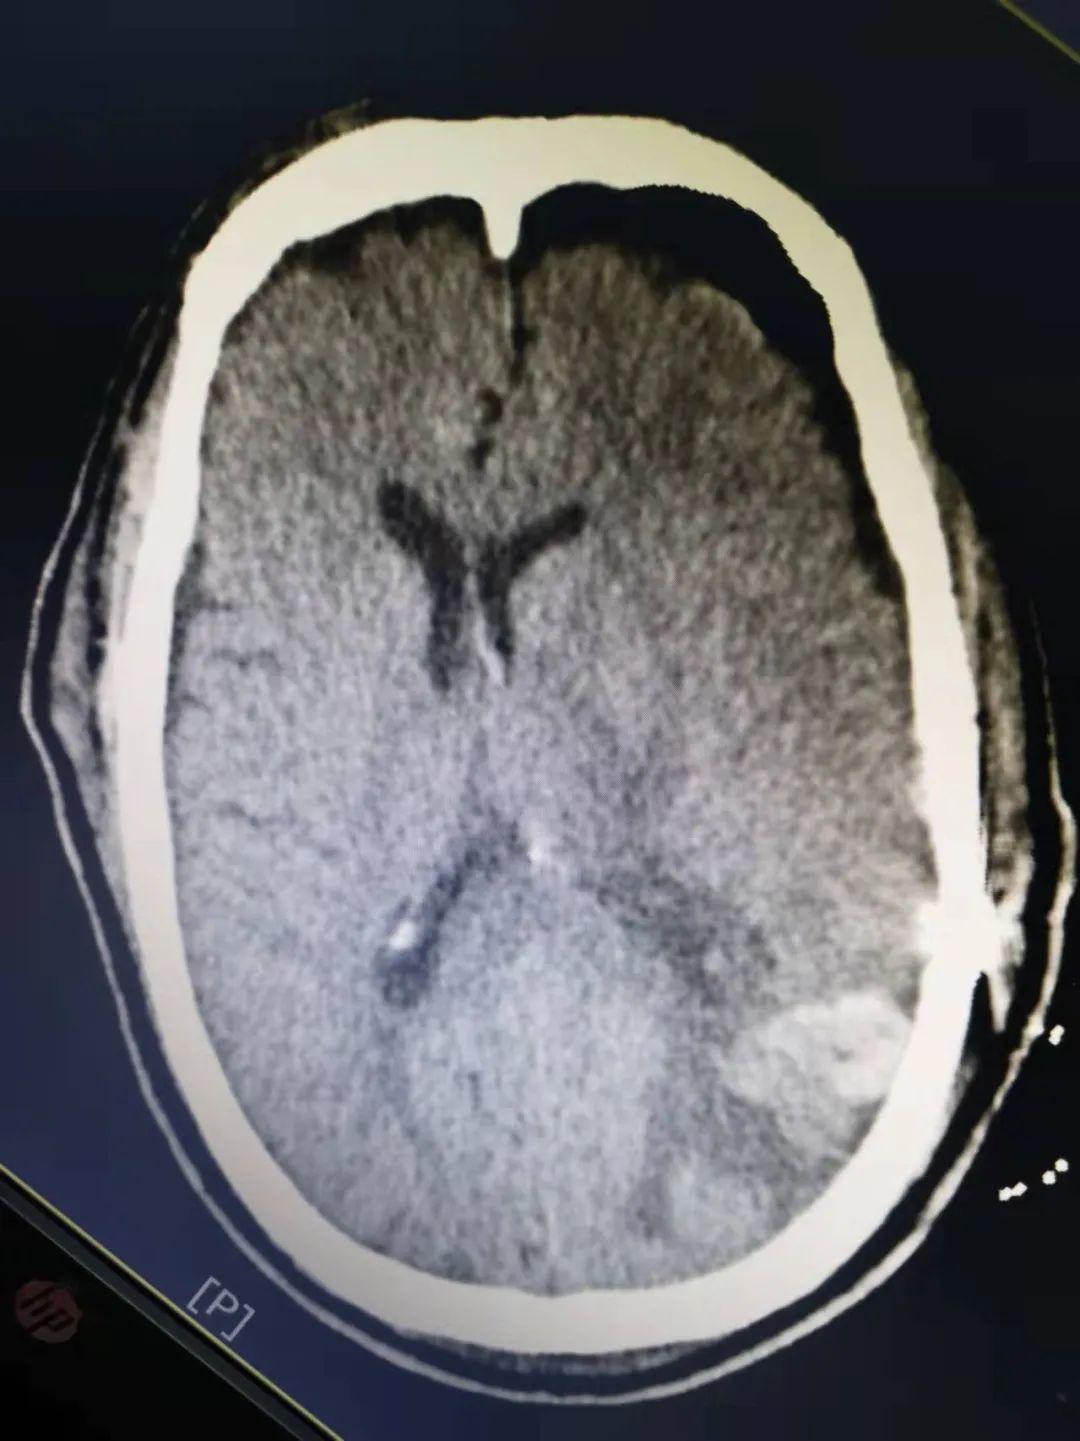

术后CT血肿清除满意